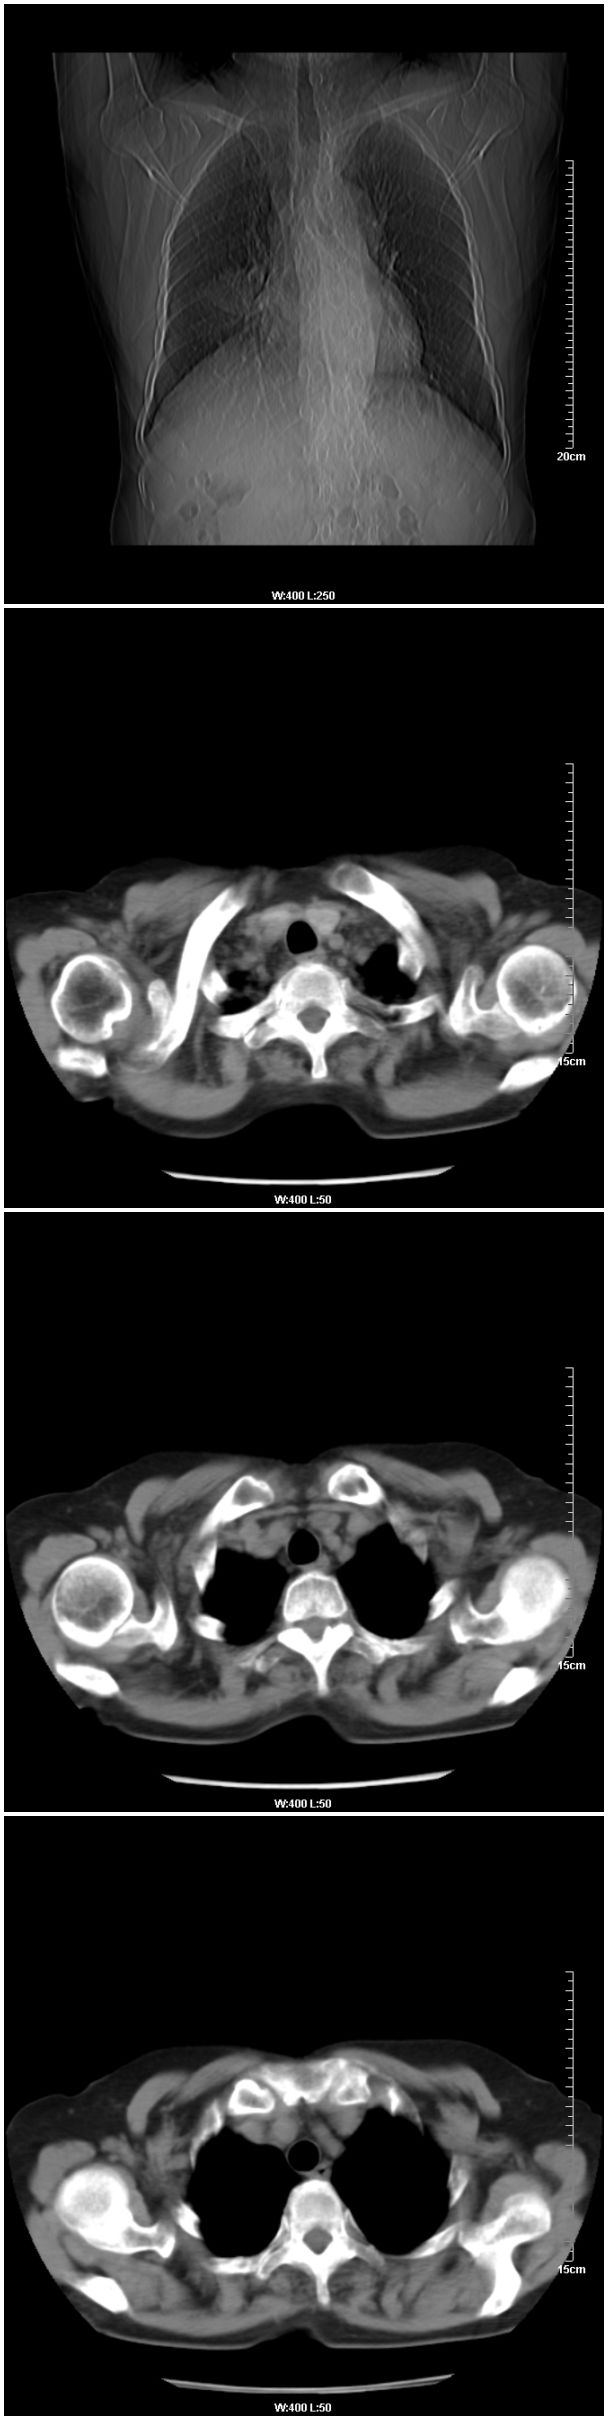

本例临床是以乳腺癌的术前检查平片发现肺部病变的,请战友们看乳腺病变是否能够看出来,在哪一侧?

在右侧,支持!右肺中心型肺癌! 右乳腺肿物。

支持!右肺中叶中心型肺癌!右侧乳腺内上象限结节,建议薄扫

乳腺病在右侧

右侧乳腺疾病.

乳腺病变在右侧   是否可考虑为乳腺癌肺部转移

应该是右肺中心型肺癌,乳腺的肿物应该在右侧,看见右侧有结节,并乳头凹陷

1.右侧乳腺病变。

右侧乳腺内上象限结节影,边缘模糊,右肺病变相邻支气管内见软组织密度影及斑点样钙化灶,考虑肺癌可能性大,建议结合纤支镜检查。

右乳腺内结节病灶,如增强扫描动脉期结节呈明显强化可考虑乳癌。

支持:1、右侧乳腺病变;